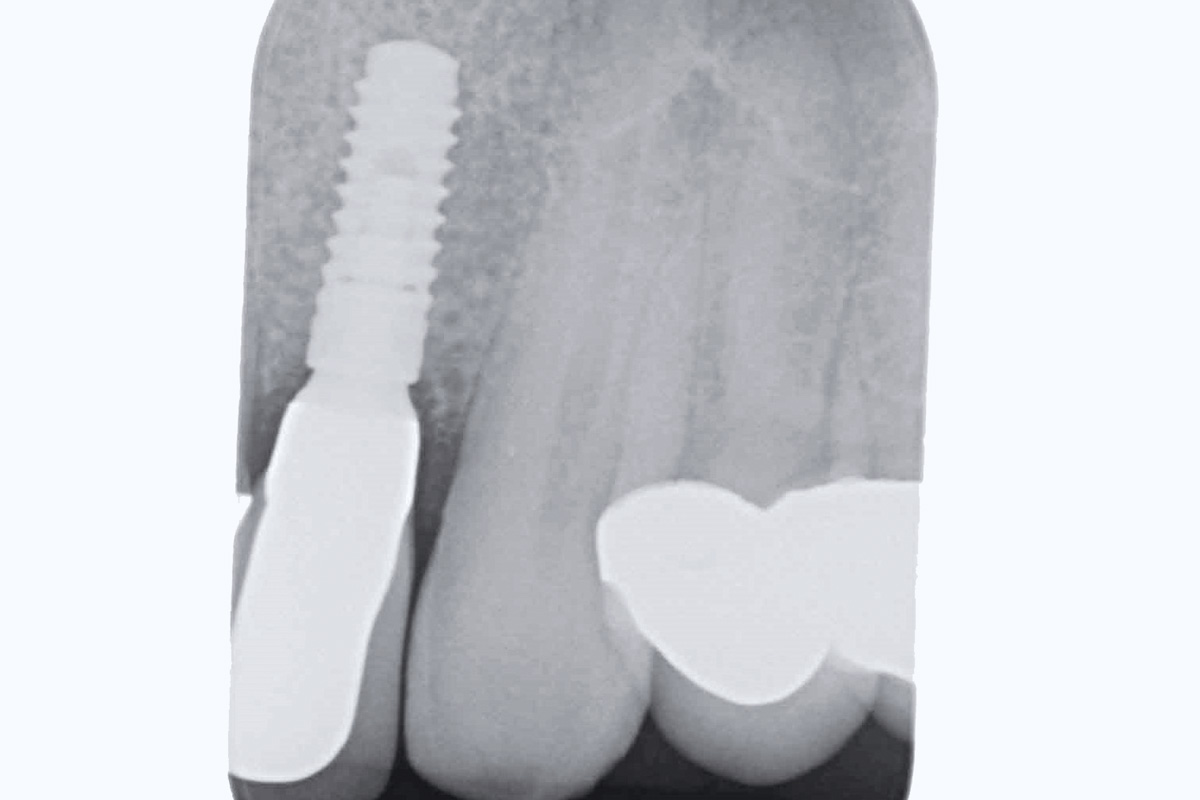

18/19 - X-ray at final restorationBone augementation with maxresorb® - Dr. R. Cutts